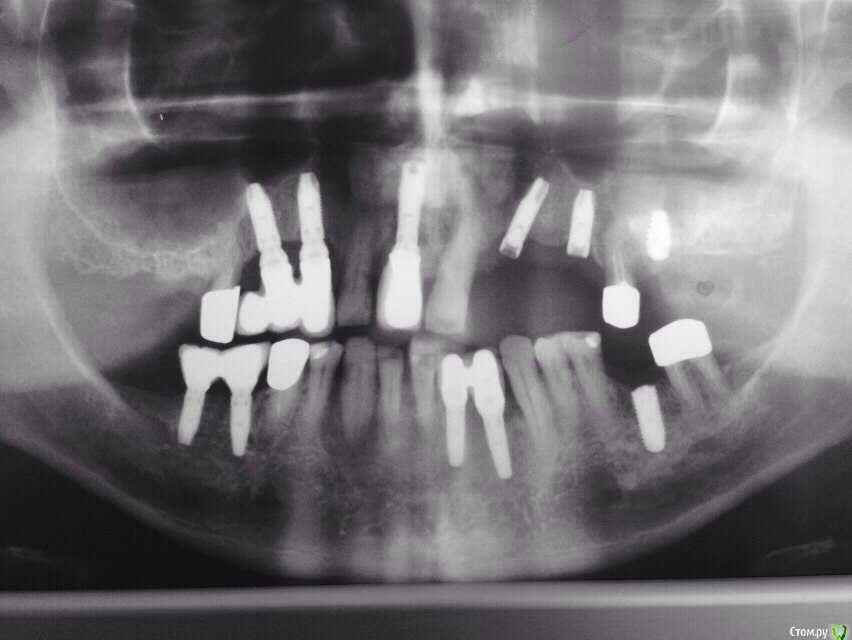

kamranchick Опубликовано 12 июля, 2015 Поделиться Опубликовано 12 июля, 2015 (изменено) Добрый день Уважаемые друзья)имеются следующие панорамники. хотелось бы посоветоваться с Вами.1, пациент обратился на затрудненное открывание рта, хотя на ширину 3 пальцев открывает рот, отправил на панорамный снимок и увидел суть проблемы. Боли начались неделю назад, боли только при открывании. слизистая слегка гиперемирована. Гигиена у пациента отличная, редко такое видел, 28 лет. у меня 2 плана, либо удаление всех 8ых зубов, либо оставить ихсмущает тот факт что пациент является профессиональным боксером, не поспособствует удаление нижних 8 зубов к перелому челюсти? и еще смущает факт очень мелкое преддверие полости рта, щеку просто не оттянуть))какие будут рекомендации и совета, из назначений было только употребление Намесил 1пак в день и полоскание мирамистином2. пациент обратился с целью протезирования, проблема в том, что он работает вахтовым методом, и постоянно в разных городах, можете ли подсказать системы имплантов которые ему установили, и какую конструкцию можно ему предложить(ибо я ортопед) от синус лифтинга отказывается, пациенту 55 лет, гигиена удовлетворительная. а так же обратно-перекрестный прикус Изменено 12 июля, 2015 пользователем kamranchick Ссылка на комментарий

viruzzz Опубликовано 16 июля, 2015 Поделиться Опубликовано 16 июля, 2015 Kamranchick:+1 за удаление всех 8-к и не забудьте про 19 зуб - выйдет легко после удаление 18.по второму снимку насчитал 5 разных видов имплантатов.. некоторые из них вызывают большие сомнения 1 Ссылка на комментарий

kamranchick Опубликовано 17 июля, 2015 Автор Поделиться Опубликовано 17 июля, 2015 вот и как протезировать) Ссылка на комментарий